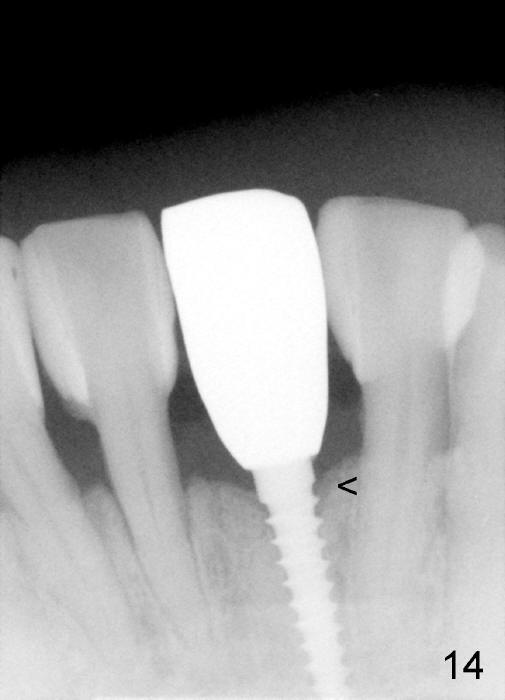

Fig.10,11 show 7 day follow up. The permanent crown is seated 4.5 months postop (Fig.12). Minimal bone resorption occurs at the crest 4 months postop (Fig.13), which is most likely associated with conservative approach (flapless). The patient returns for follow up 2.5 months post cementation (Fig.14,15). The implant remains in the bone 4 years post cementation (Fig.16 CT coronal section; lingual thread exposure, corresponding to preop defect in Fig.1). There is mild coronal bone resorption 5 years 4 months post cementation (Fig.17).